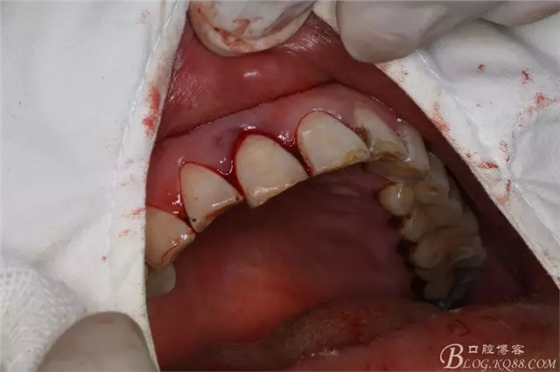

圖2.右上11唇側(cè)根尖區(qū)牙齦紅腫,捫痛明顯、叩診(++)

圖3.腭側(cè)牙周袋深約8mm.